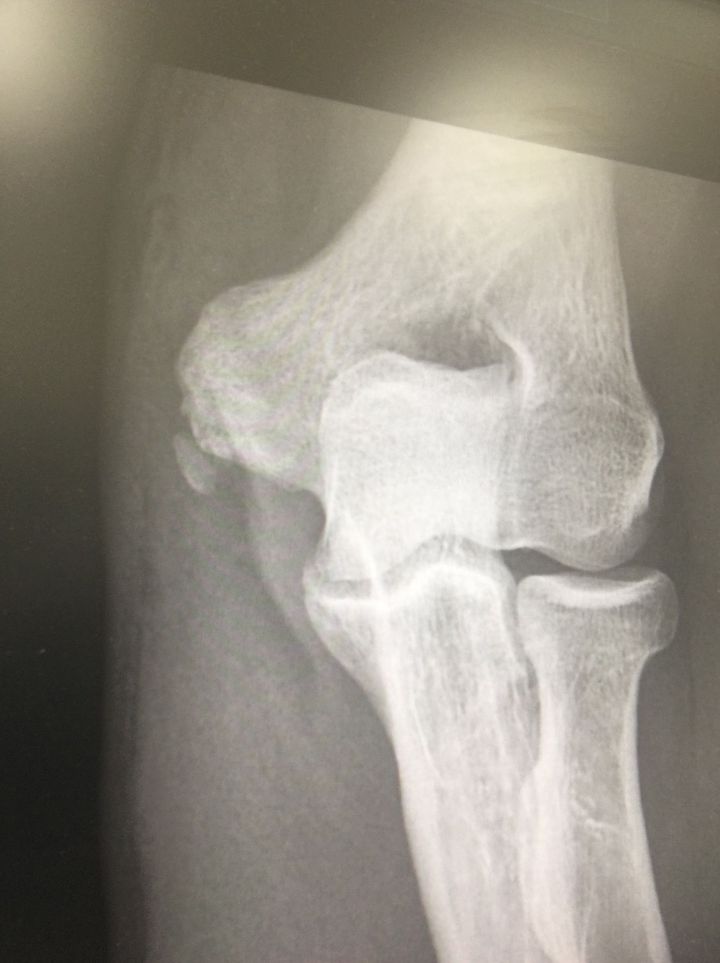

#pain in elbow region and the patient age 44y

Communtive # medial epicondyl?

Bone spur?

lateral epicondylitis (tennis elbow)?